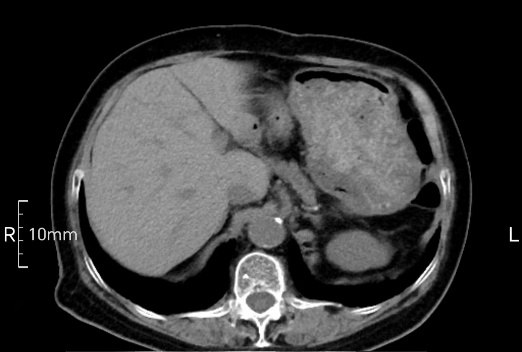

看看下面三幅便知遵醫(yī)囑的重要性。

沒禁食,胃內(nèi)全是食物,導(dǎo)致胃壁顯示不清。

禁食但檢查前沒有喝飽,胃未能漲開,胃壁觀察效果不佳。

完美禁食且喝飽飽,胃壁完美展現(xiàn)。

CT檢查前的“禁食”和“喝飽”,看似矛盾,實(shí)則合情合理,分工合作:空腹:是為了讓上腹部(肝膽胰脾腎等)的圖像清晰無干擾,并保障檢查安全。喝水:有效的充盈胃部和、腸道使圖像清晰呈現(xiàn)。兩者巧妙配合,都是為了給您一個最精準(zhǔn)的診斷結(jié)果。